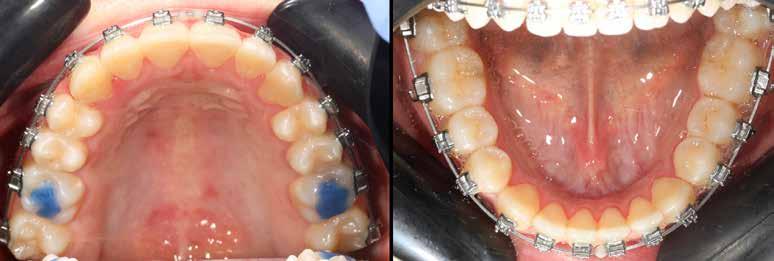

A vegyes fogazati kezelési célok a fogívek tágítása és a mandibula meziális irányú növekedésének a biztosítása volt. Fontos, hogy az ilyen típusú készülékeket nem csak éjszaka, hanem napközben is – amennyit csak lehet – hordani kell a minél hatékonyabb működés érdekében. A 18 hónapos első fázisú kezelésnek köszönhetően az alap kezelési célok megvalósultak, sikerült a class 1-es okklúziót beállítani (4-7. képek).

terséges harapásemelés pedig az alsó hatosokra, majd később a felső négyesekre került (8. kép). Az intermaxilláris elasztikus gumihúzás class-2-ess vektorú volt annak érdekében, hogy a disztálharapás korrekciója tökéletes legyen (9. kép). A harapást beállító elasztikus gumihúzásokat – mint minden kezelésnél –, ebben az esetben is folyamatosan, az egész kezelés alatt 24 órában (étkezések kivételével) viselte páciensünk.

A második Pitts-21 fix készülékes fázis ideje 16 hónap volt (10-12. képek)